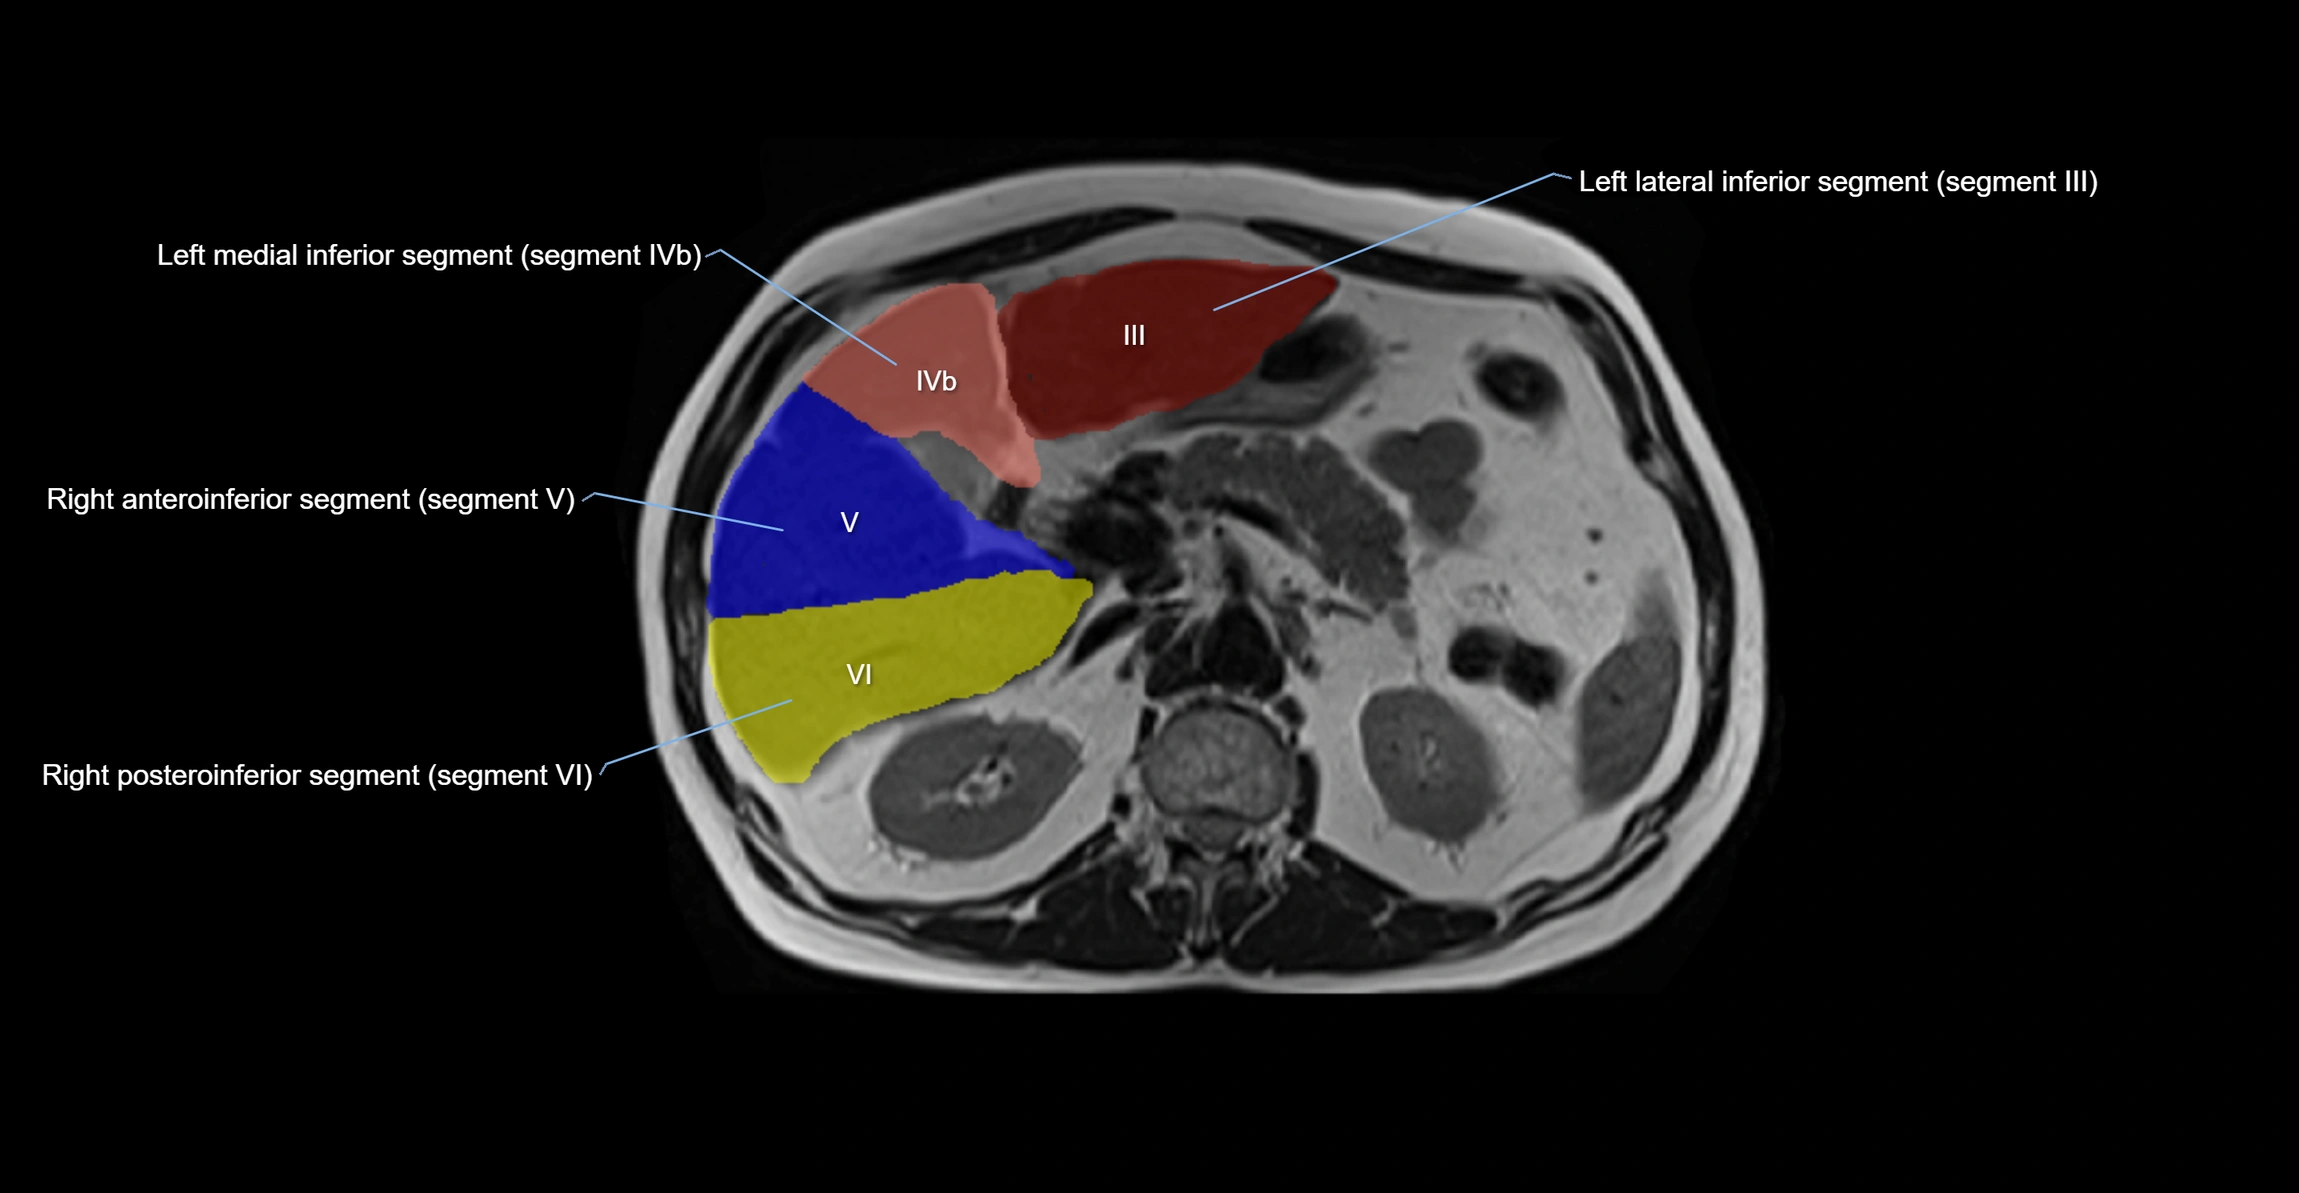

The caudate lobe of the liver is a distinct anatomical subdivision of the liver, designated as segment I in Couinaud’s classification. It lies on the posterior surface of the liver, between the fissure for the ligamentum venosum (left boundary) and the groove for the inferior vena cava (IVC) (right boundary). Superiorly, it is related to the posterior liver surface, and inferiorly it is separated from the left lobe by the porta hepatis.

The caudate lobe is unique because it receives dual portal venous and arterial inflow from both the right and left portal veins and hepatic arteries. It also has independent venous drainage directly into the IVC via multiple small hepatic veins, unlike other lobes that drain through the three main hepatic veins.

This anatomical autonomy makes the caudate lobe especially significant in liver surgery, transplantation, and hepatic venous outflow obstruction syndromes (e.g., Budd–Chiari syndrome). Enlargement of the caudate lobe is a characteristic imaging feature in chronic liver disease and cirrhosis.